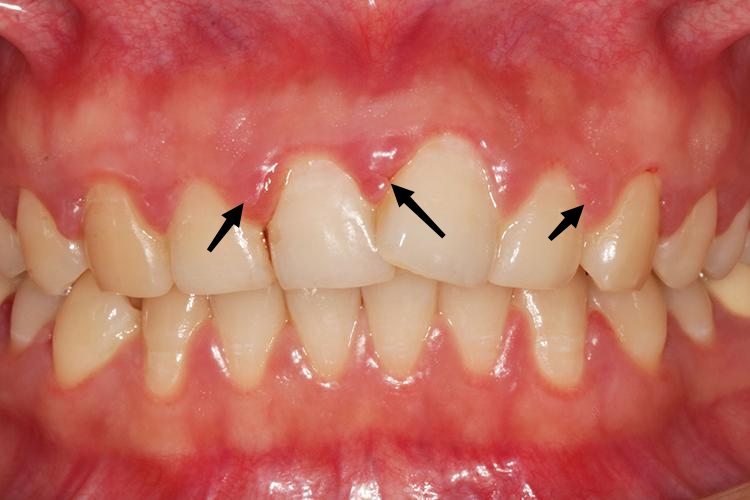

妊娠期龈炎

妊娠前即有慢性龈炎,从妊娠2~3个月后出现明显症状,至8个月达到高峰,分娩后约2个月龈炎可减轻至妊娠前水平。炎症可发生于个别牙龈或全口牙龈,以前牙区为重。患者常因吮吸或进食易出血而就诊。龈缘和龈乳头呈鲜红或暗红色,松软光亮,有龈袋形成,轻探易出血。一般无疼痛。